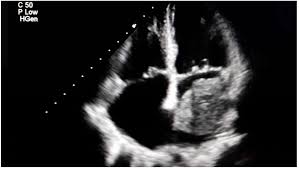

A 72-year-old woman is presenting to a Cardiologist following a referral from her PCP. Her PCP heard a heart murmur on a routine visit and was concerned since the pt does not have a history of heart problems. Pt had an echocardiogram performed the day prior but it’s still unread by a Cardiologist. They send you (a medical student) in to interview the pt and perform a physical exam. Her history is unremarkable. On physical exam, you auscultate her valves and hear a distinct rumble in diastole in all locations, however it’s loudest around the apex of the heart. You tell your attending, who takes a look at the echo who finds the following image. The most likely diagnosis is….

Atrial myxoma